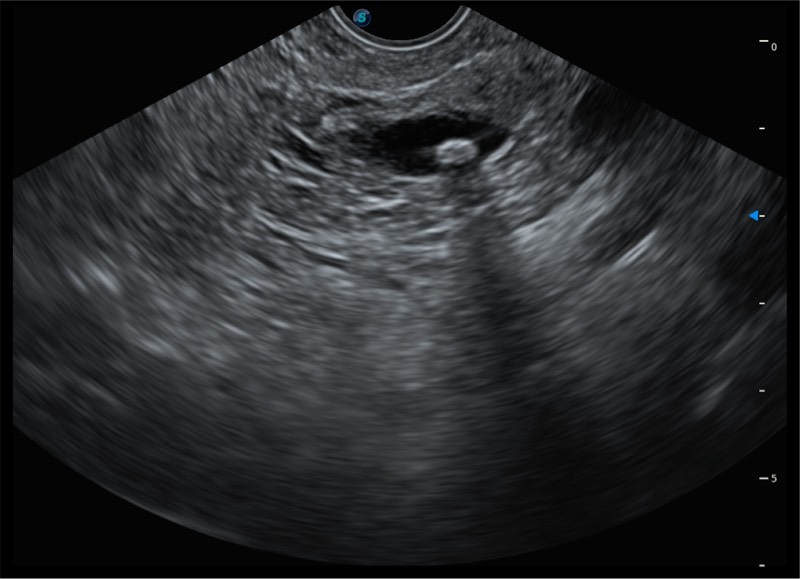

• 搭载百万级CMOS成像技术

• 及自主研发凸阵换能器,

• 可呈现优质的内镜和超声画面

基于二十年的超声技术积累,玖鼎集团提供了最新一代的独立超声主机,在提供高质量图像的同时满足多学科使用。具备常见多普勒技术并提供弹性成像、声学造影等高端影像技术。新一代传感器具有更强的抗干扰能力并减少图像伪影。

• 4-12MHZ宽频输出